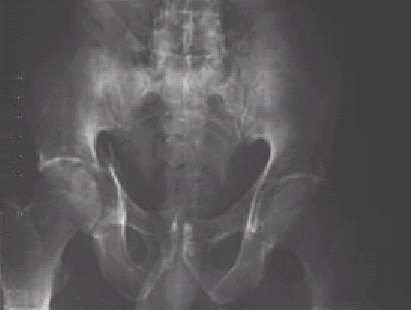

Figura 4.—Fractura unilateral derecha de pelvis y del muro anterior del cotilo derecho, proyección AP simple de pelvis.